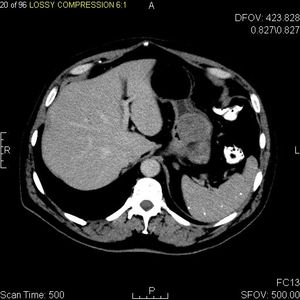

5. 1. 영상 검사

CT 스캔과 MRI는 GIST를 평가하는 데 선호되는 영상 검사 방법이다. 작은 GIST는 대개 점막하 종양 또는 장벽 내 종괴로 나타난다. 바륨 연하 검사에서 이러한 GIST는 인접한 장벽과 직각 또는 둔각을 이루는 매끄러운 경계로 나타나며, 점막 표면은 대개 손상되지 않지만, 50%에서 궤양이 나타나기도 한다. 궤양은 바륨으로 채워져 과녁 또는 표적 병변처럼 보인다. 조영 증강 CT에서 작은 GIST는 균질한 감쇠를 보이는 매끄럽고 선명하게 정의된 장벽 내 종괴로 보인다.큰 GIST는 장 밖으로 튀어나오거나 장 내부로 성장할 수 있으며, 내부에서 괴사(죽음)하여 결국 장 내강과 소통하게 될 수 있는 공동을 형성한다. 공동 형성이 있는 경우, 단순 방사선 촬영에서 종양 내 공기 덩어리가 나타날 것이다. 석회화는 GIST의 드문 특징이지만, 존재할 경우 단순 촬영에서 볼 수 있다.

악성 GIST는 국소 침윤과 전이를 특징으로 하며, 전이는 주로 간, 대망, 복막으로 발생한다. 그러나 뼈, 흉막, 폐, 후복막으로의 전이 사례도 보고되었다. 위 선암종 또는 위/소장 림프종과 달리, 악성 림프절병증 (부어오른 림프절)은 드물며 (<10%) 따라서 영상 검사에서는 림프절 비대가 없는 경우가 많다. 전이가 없는 경우, 악성을 시사하는 다른 방사선학적 특징으로는 크기 (>5 cm), 조영제 투여 후의 불균일한 조영 증강 및 궤양이 있다.[12]